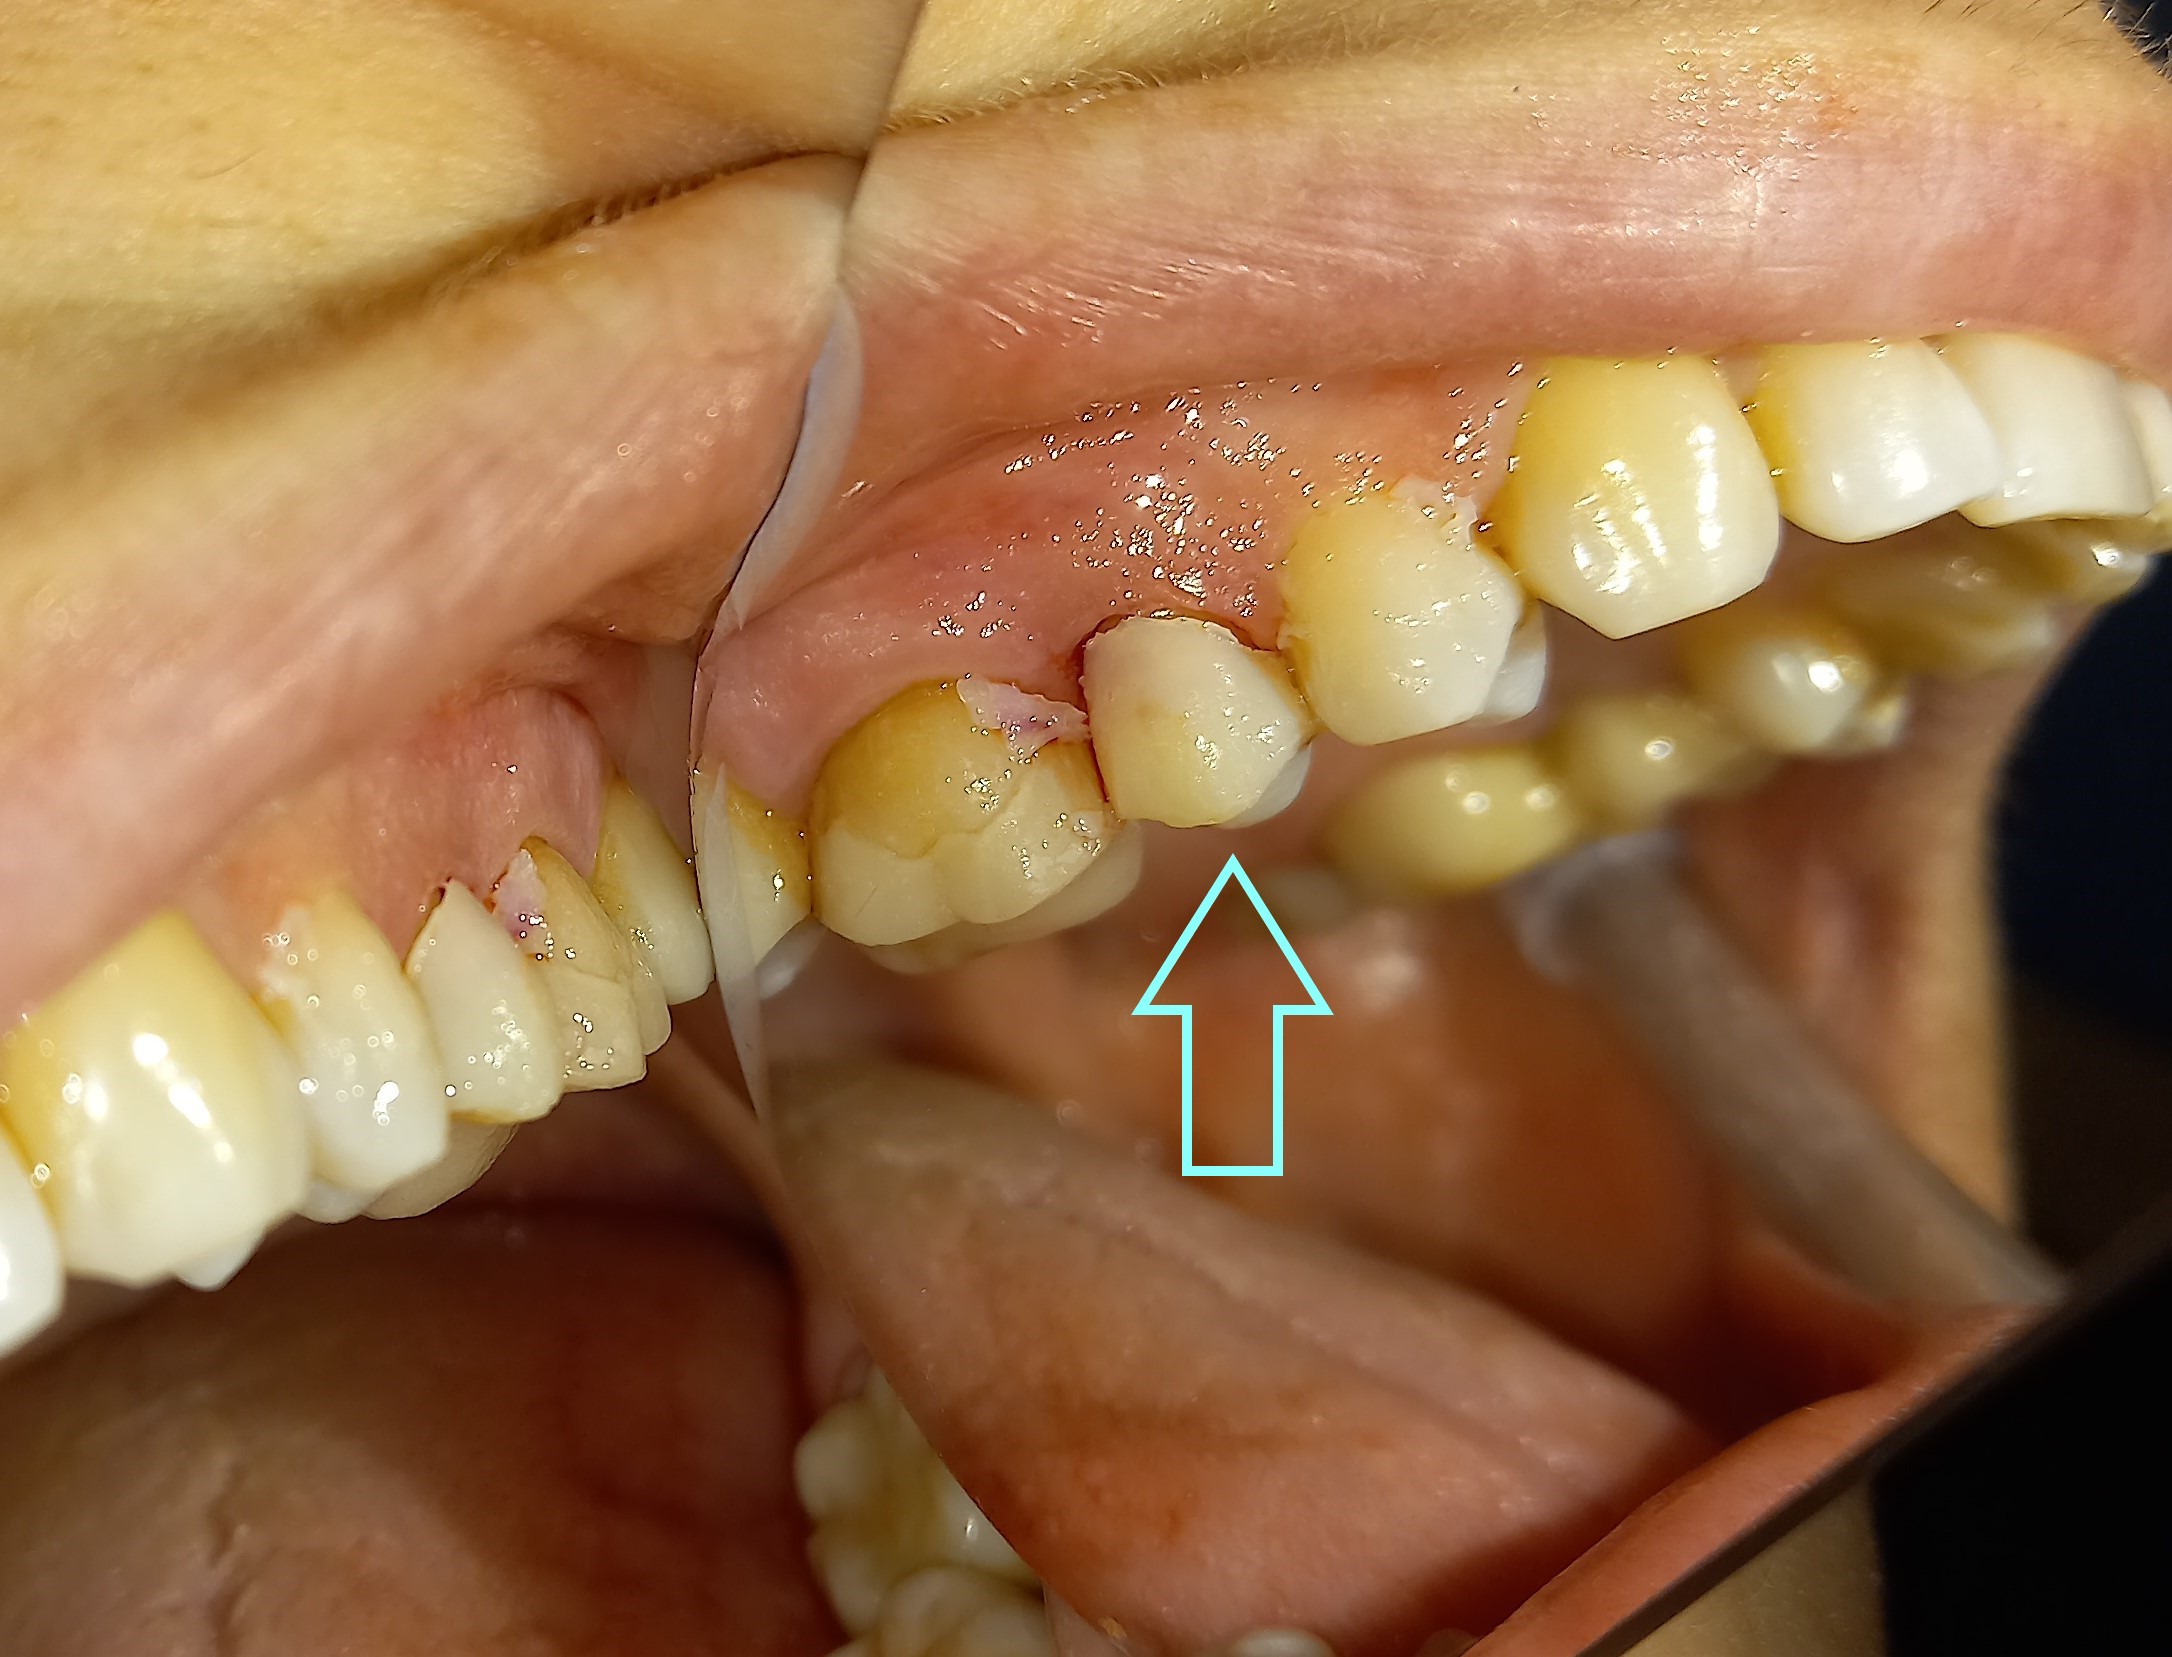

Είναι σημαντικό κατά τη διάρκεια μιας προσθετικής εργασίας τα δόντια να καλύπτονται από προσωρινή θήκη. Τα πλεονεκτήματα της προσωρινής θήκης είναι η προστασία που παρέχει στα δόντια από πιθανό σπάσιμο ή και από πόνο που ίσως να προκαλέσει η λήψη ψυχρών ποτών και τροφών. Επίσης τα ούλα γύρω από τα δόντια με προσωρινή κάλυψη παραμένουν στη θέση τους και δεν παρατηρείται υπερπλασία με αποτέλεσμα η μόνιμη προσθετική εργασία να εφαρμόζει άψογα πάνω στα δόντια, χωρίς να χρειάζεται να τροποποιηθούν τα ούλα.

Στο συγκεκριμένο περιστατικό η προσωρινή θήκη κατασκευάστηκε στο ιατρείο.